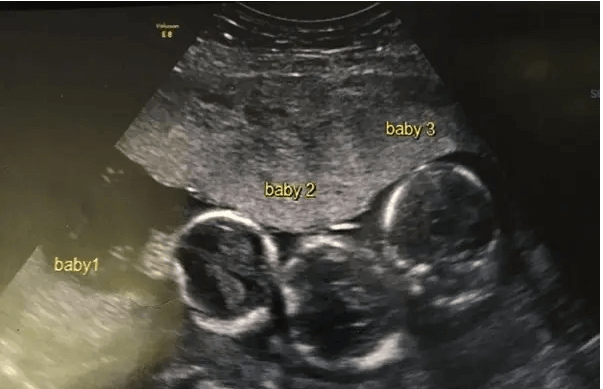

Yet, this story took an unexpected turn for Becki Allen. The revelation from the doctors left her astounded. Statistically, her situation was a rarity, occurring once in every 200 million cases.

The contented family from Liverpool, England, had aspirations of building wealth and expanding their family, but the revelation of having multiple children at once was beyond their expectations—triplets! And not just triplets, but three identical ones.

During Becki’s pregnancy, she grappled with severe headaches, prompting doctors to conduct an ultrasound for reassurance.

Speaking to the Liverpool Echo, Becki shared, “It was the most shocking moment of my life! There’s no history of triplets in our family, so this news was completely unexpected.”